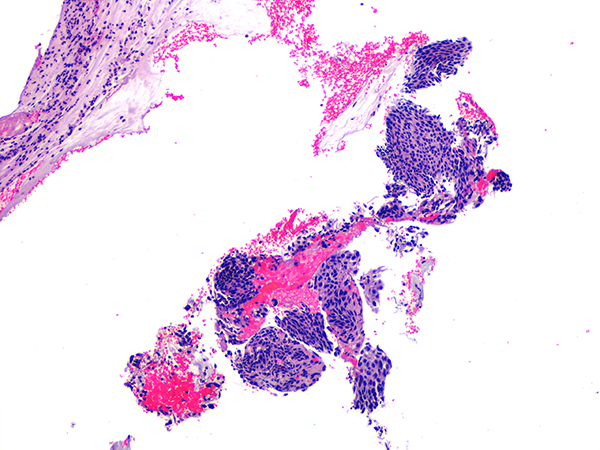

Case 2

Soft Bx CIN 2 10x - Low Power |